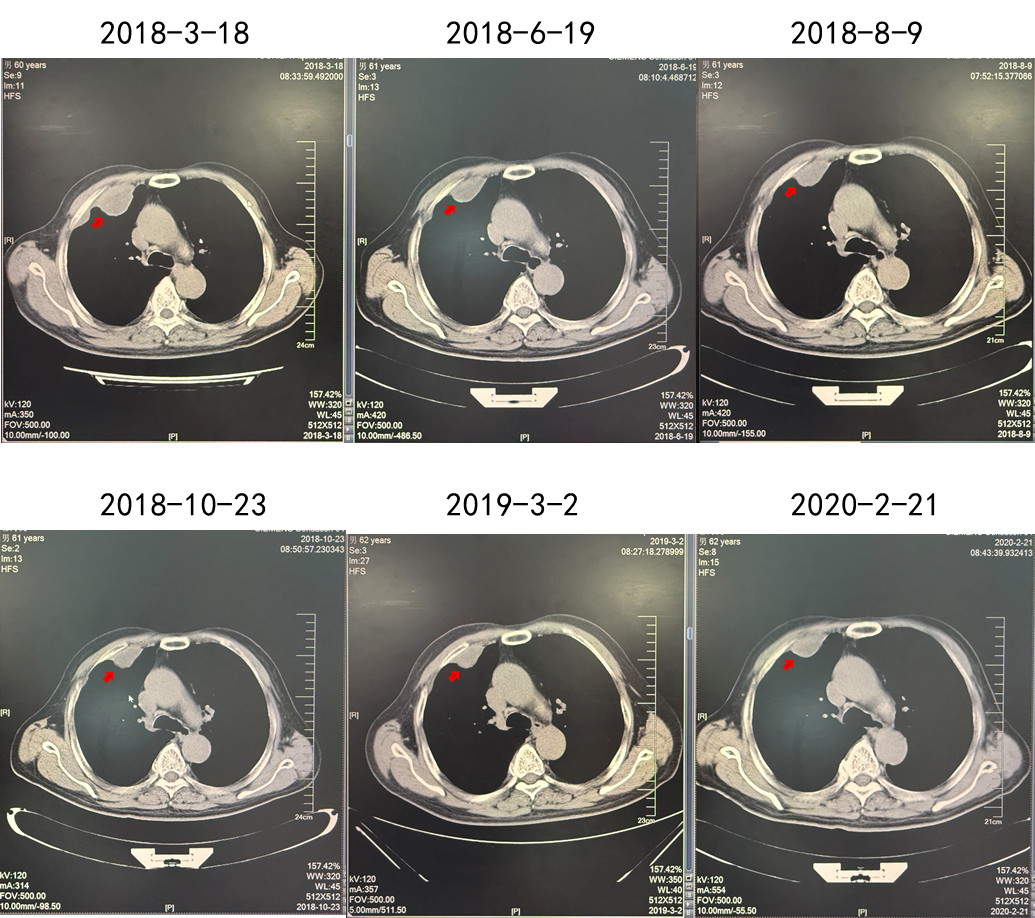

疗效:肋骨病灶疾病稳定(2年),肺部病灶部分缓解(2年)。

(舒尼替尼单药联合放疗,肋骨病灶实现SD)

(舒尼替尼单药联合放疗,肺转移病灶实现PR)